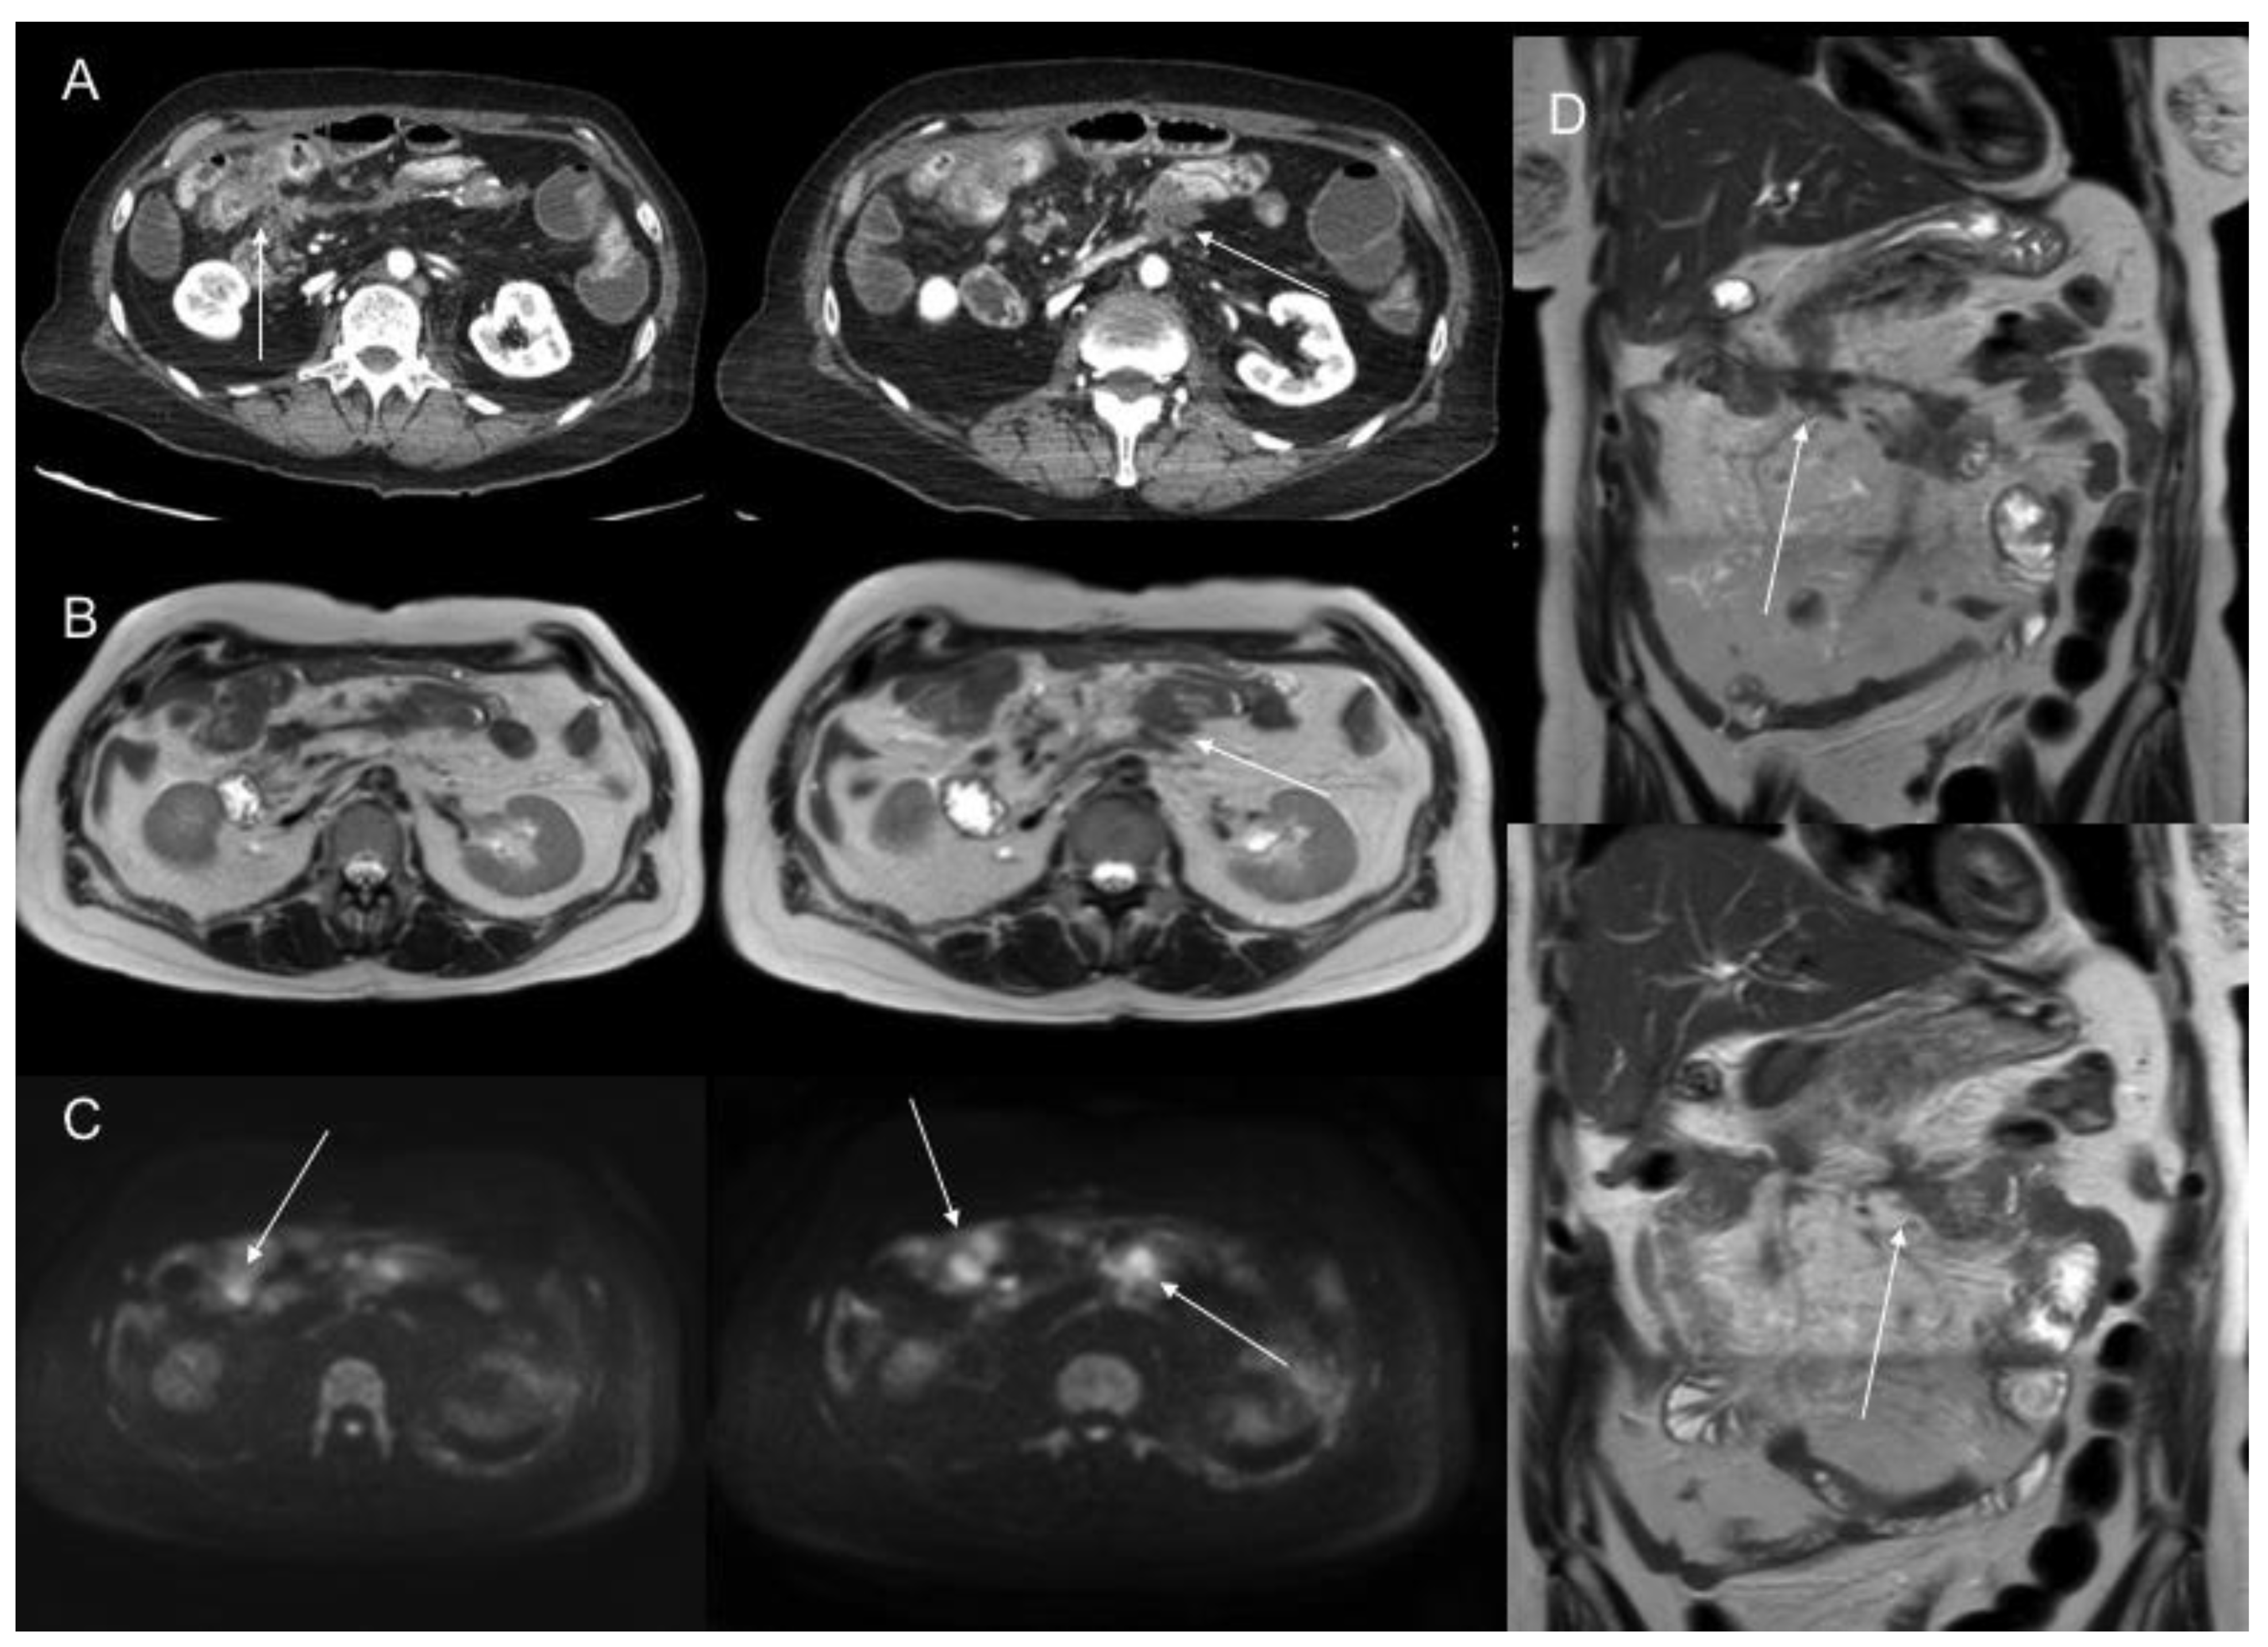

- De Vuysere, S.; Vandecaveye, V.; De Bruecker, Y.; Carton, S.; Vermeiren, K.; Tollens, T.; De Keyzer, F.; Dresen, R.C. Accuracy of whole-body diffusion-weighted MRI (WB-DWI/MRI) in diagnosis, staging and follow-up of gastric cancer, in comparison to CT: A pilot study. BMC Med. Imaging 2021, 21, 1–9. [Google Scholar] [CrossRef] [PubMed]